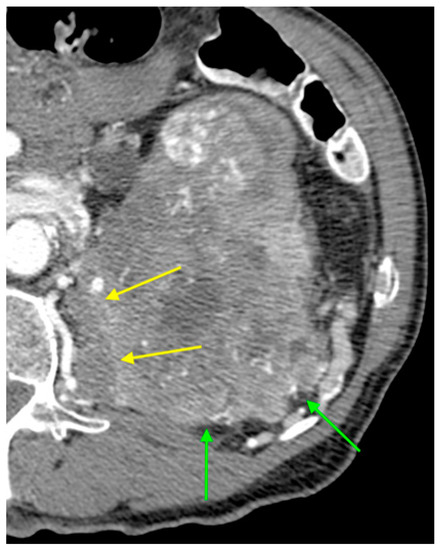

| Signs of infiltration | 4 (2.1%) | 0 (0.0%) | 4 (7.7%) | 0.005 c |